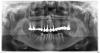

Doc Опубликовано 24 августа, 2012 Поделиться Опубликовано 24 августа, 2012 По одной ортопантомограмме сложно сказать что там можно и нужно делать. У Вас, возможно, есть еще проблемы с прикусом, а их на орто не особо увидишь. В любом случае внизу с двух сторон нет никаких моляров, значит минимум по два с каждой стороны нужно, если не больше. По верху тоже сложно сказать. Стопроцентных показаний все снимать и переделывать на снимке нет, а что там во рту мы не знаем. Покажитесь стоматологам лично, тогда будет предметный разговор. Ссылка на комментарий

xuxu Опубликовано 24 августа, 2012 Автор Поделиться Опубликовано 24 августа, 2012 По одной ортопантомограмме сложно сказать что там можно и нужно делать. У Вас, возможно, есть еще проблемы с прикусом, а их на орто не особо увидишь. В любом случае внизу с двух сторон нет никаких моляров, значит минимум по два с каждой стороны нужно, если не больше. По верху тоже сложно сказать. Стопроцентных показаний все снимать и переделывать на снимке нет, а что там во рту мы не знаем. Покажитесь стоматологам лично, тогда будет предметный разговор. Да, проблема с прикусом есть, это врач мне на консультации уже сказал. Относительно верха, врач сказал, что на последних зубах, не поняла правда с какой стороны, восполение у корней, поэтому все переделывать. И еще проблема в передних зубах. 2 коронки отвалились и необходимо удалять корни и ставить импланты. Врач говорит, что ничего постепенно делать нельзя, т.е. нельзя сейчас поставить 2 передних импланта и потом делать дальше. Или сразу все или никак. Ссылка на комментарий